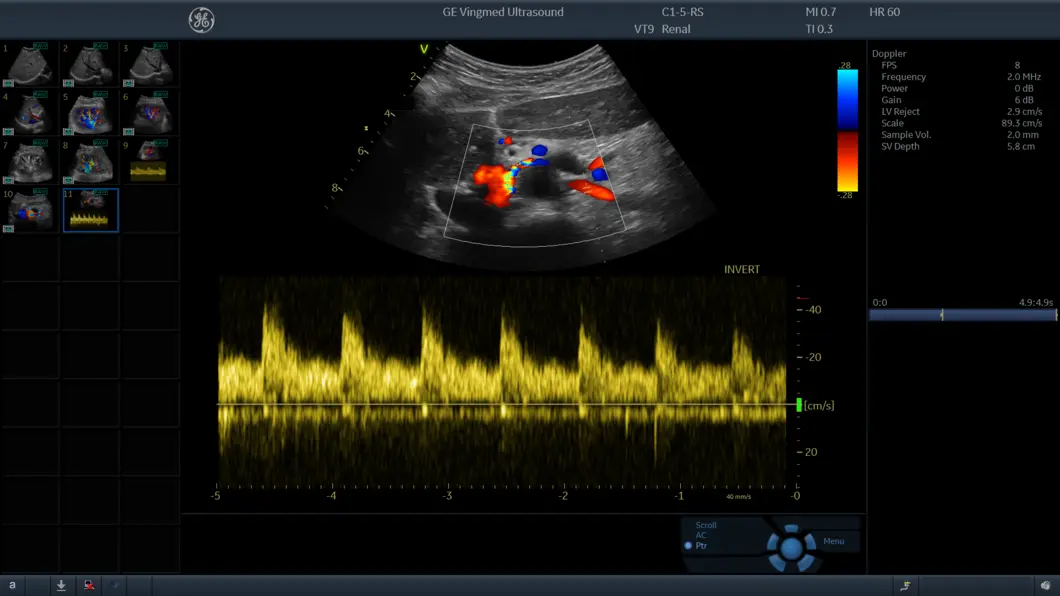

Режим цветового тканевого Доплера (TVI)

Отображает динамическую информацию от движущихся тканей сердца, позволяя с легкостью определять функцию левого желудочка.